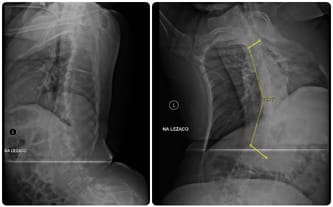

Desminopatia, postępująca skolioza kręgosłupa